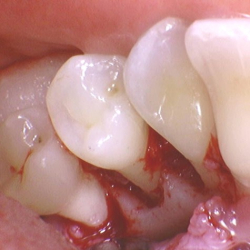

• Patientvurdering og parodontal diagnostik

• Systematisk journaloptag, risikovurdering og kliniske målinger